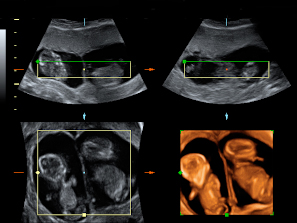

Ecografía Embarazo 2D y 3D Semana 12 - ANOMALÍAS CROMOSÓMICAS